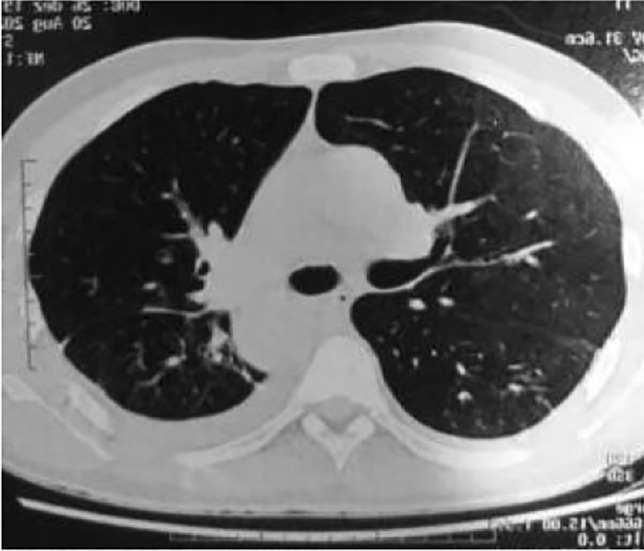

In our research group, we revised the clinical records of a 49-year-old male patient, unvaccinated, with a confirmed laboratory diagnosis of coronavirus disease (immunological diagnosis). In addition, chest computed tomography (CT) evaluation was performed (Fig. 1). The patient presented with seizures, with no known comorbidities, followed by cardiac arrest. The investigation proceeded with neuroimaging that revealed bilateral brain calcifications (as shown in Fig. 2). Unlike the case described by Demir (2020), where ectopic calcinosis was linked to a hormonal etiology, our patient would be diagnosed as having primary or idiopathic brain calcifications. After discharge and follow-up, the patient’s immunization status has changed. Concerning neurological manifestations, he is now asymptomatic.

Fig. 1.

Chest computed tomography (CT)